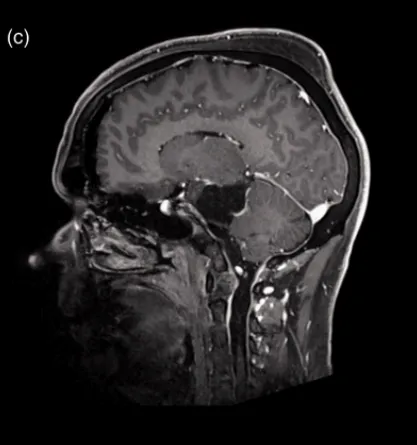

术后状况

手术实现了肿瘤的完全切除,周围的IV、V、VII、VIII和VI对颅神经均得以保留,患者在术后神经学功能保持正常。术后进行的脑部MR检查显示脑膜瘤已部分去血管化,未见脑水肿现象。手术后,除了患者新发头痛外,临床检查结果未见其他变化。